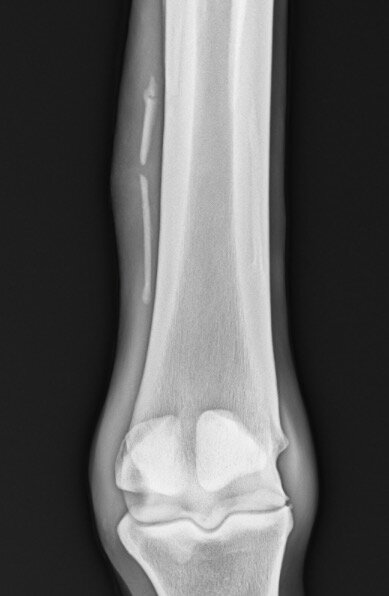

Ibbel schreef:Ik kan me niet voorstellen wat er mis zou kunnen gaan of wat de contra-indicaties van een operatie aan het griffelbeentje zouden kunnen zijn. Gebroken griffelbeentjes genezen niet, het afgebroken deel zal na verloop van tijd wel ingekapseld worden, maar dan heb je een los botfragment onderhuids zitten wat op allerlei structuren kan gaan drukken.

Cowgirl schreef:Ik zou die foto's opsturen naar een goede paardenkliniek en hun een oordeel laten maken.

Het ziet er behoorlijk heftig uit alhoewel ik ooit eens foto's gezien heb van en paard waarbij het gewoon verbrijzeld was..Daar konden ze niks mee, paard zou blijvende schade houden. Dier is dan ook ingeslapen.